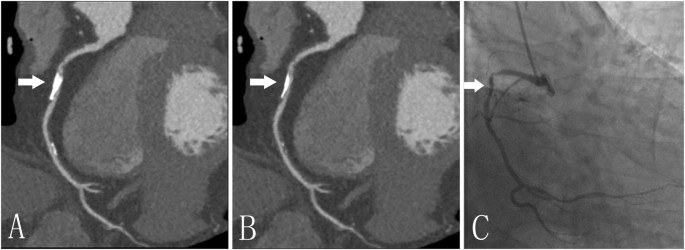

The volume of calcified plaques with the de-blooming algorithm decreased from 35.1 ± 26.5 mm3 to 19.3 ± 15.8 mm3 (p < 0.0001); While coronary diameter stenosis decreased from 34.7 ± 21.4% to 18.4 ± 15.4% (p < 0.0001); coronary area stenosis decreased from 50.1 ± 24.6% to 27.2 ± 19.8% (p < 0.0001). The reduction of calcification volume was 48.1 ± 10.3%, while reduction of coronary diameter stenosis was 52.4 ± 24.2%; and coronary area stenosis reduction over calcified plaque was 51.1 ± 23.3%. Figure 3 provides a representative example with and without use of de-blooming algorithm.

A 77-year-old man with calcified plaque (arrow) of the right coronary artery. A and B, Curved planar reformation (CPR) images without (A) and with (B) de-blooming algorithm show the volume reduction of calcified plaque and improvement of lumen evaluation by using this algorithm; (C) Invasive coronary angiography confirms mild stenosis in the right coronary artery. Without de-blooming algorithm, the right coronary artery was almost occluded; while with use of de-blooming algorithm, the right coronary artery was almost 50% stenosis, being consistent\ with findings from invasive coronary angiography.